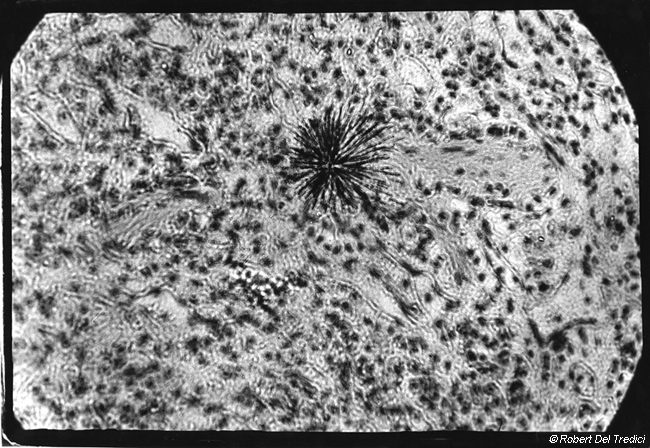

D5. Particle of Plutonium in Lung Tissue. The black star in the middle of this picture shows tracks made by alpha rays emitted from a particle of plutonium embedded in the lung tissue of an ape. Alpha rays do not travel very far. They are harmless outside the body, but once inside they can damage more than 10,000 cells within their range. Alpha emitters are among the most deadly of radioactive materials. Radon gas, radium, plutonium, and polonium are alpha emitters. After 1,000 years, the main hazard from irradiated nuclear fuel is due to its long-lived alpha emitters. The tracks in the photograph were made by bursts of alpha-radiation over a 48-hour period. Lawrence Radiation Laboratory, Berkeley, California. 20 September 1982.